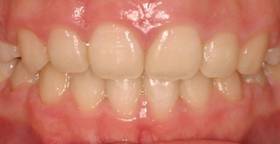

上顎前突+叢生 抜歯矯正(治療期間1年)

治療前、特に上の歯並びに問題がありました

奥歯のかみ合わせもよくありません

口元が突出しています